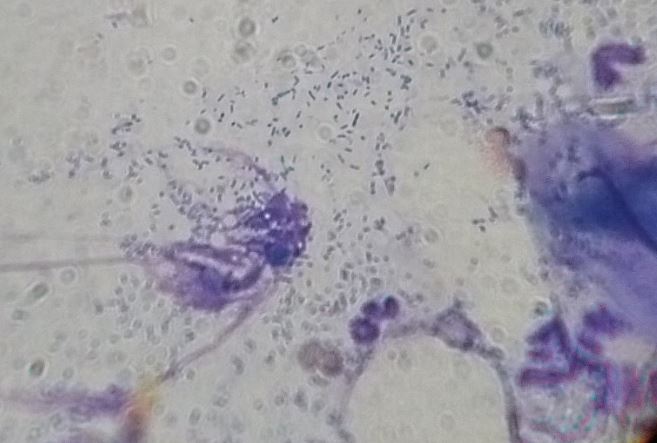

Eine ganz wichtige Untersuchung ist die Zytologie. Man rollt einen Wattetupfer auf einem Objektträger aus und färbt ihn an. Nun kann man erkennen, ob im Ohr ein Pilzproblem oder ein Befall mit Stäbchenbakterien oder Kokken vorliegt. Hat man den Überblick nimmt man einen zweiten Tupfer für die bakterilogische Untersuchung. Da diese Untersuchung ein paar Tage dauert kann man sich nun einer ausgiebigen Reinigung des Gehörganges widmen.